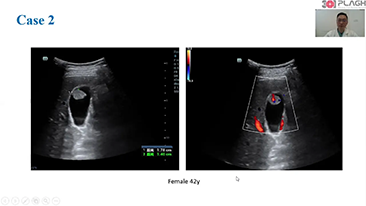

Zorg met minder stethoscoop, meer echografie?

Geoptimaliseerde workflows in gynaecologie en verloskunde zijn noodzakelijk ter ondersteuning van grote pati?ntenvolumes aan screeningbezoeken voor vrouwen. Misvormingen van het centrale zenuwstelsel (CZS) zijn bijvoorbeeld een van de meest voorkomende aangeboren afwijkingen. Als gevolg van verschillende beeldvormingscondities, zoals een slechte foetale positie, is de MSP zeer moeilijk te vinden in een 2D-echografie. Daarom kunnen geautomatiseerde detectie en metingen de scaneffici?ntie sterk verbeteren.